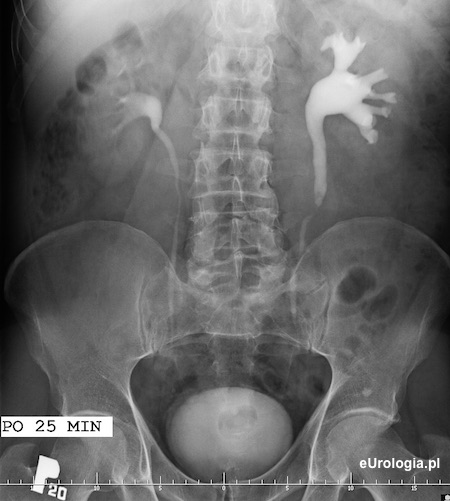

Wodonerczowato poszerzony UKM lewej nerki i lewy moczowód aż do opisywanego na zdjęciu cienia - złóg w lewym moczowodzie.

Złóg o wymiarach 10x7 milimetrów w górnym odcinku lewego moczowodu